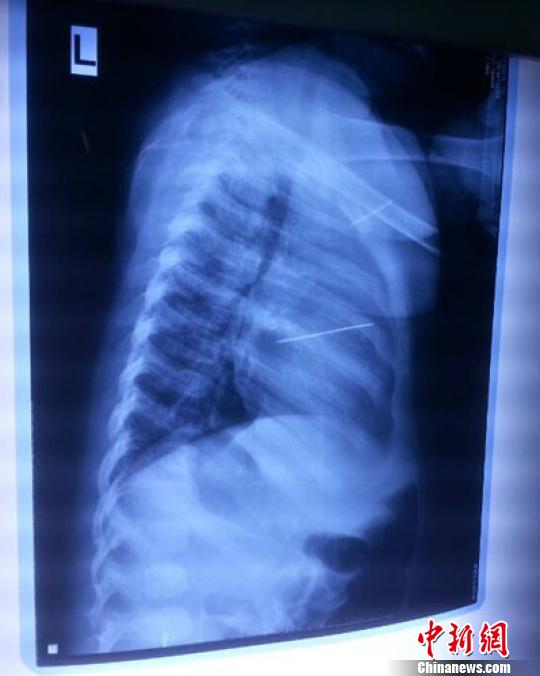

女嬰胸片提示心臟里面扎了一個(gè)縫衣針 蔡迅翔 攝

醫(yī)院胸心外科主任翟波介紹說,1月22日,小患者彤彤因?yàn)榘l(fā)燒抽搐來醫(yī)院就診,常規(guī)檢查時(shí)發(fā)現(xiàn)孩子心臟里面扎了一個(gè)縫衣針。

“第二天上午,我們做了個(gè)緊急彩超檢查,發(fā)現(xiàn)針是從患者右心室表面刺入,穿破室間隔,到達(dá)左心房,中間還有一部分損害到二尖瓣。于23號(hào)下午,我們就做了一個(gè)緊急手術(shù),手術(shù)中發(fā)現(xiàn),這枚針已經(jīng)刺入心臟,沒入了右心室的下面,表面已經(jīng)看不到針了,僅能看到一個(gè)小針眼,還在往外滲血,一點(diǎn)一點(diǎn)的滲,心包腔里面大概有100多毫升的出血,心包上一個(gè)洞,針在右心室表面刺入以后,穿過室間隔,在二尖瓣的上方,進(jìn)入了左心房,在針的四周,有很多纖維沉積物,包繞著這枚針?!钡圆ㄕf,他們把針取出來以后,測量了一下,長度大概是五厘米,同時(shí)發(fā)現(xiàn)這個(gè)針給患者左心房的后壁造成了一定的損傷,左心房的后壁已經(jīng)損傷了三分之二,還剩下有左心房的外膜,很薄的一層,如果這一層再破的話,這個(gè)孩子將會(huì)引起大出血,很快就會(huì)死亡。